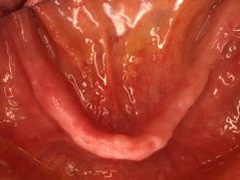

義歯の内面

装着時

装着後